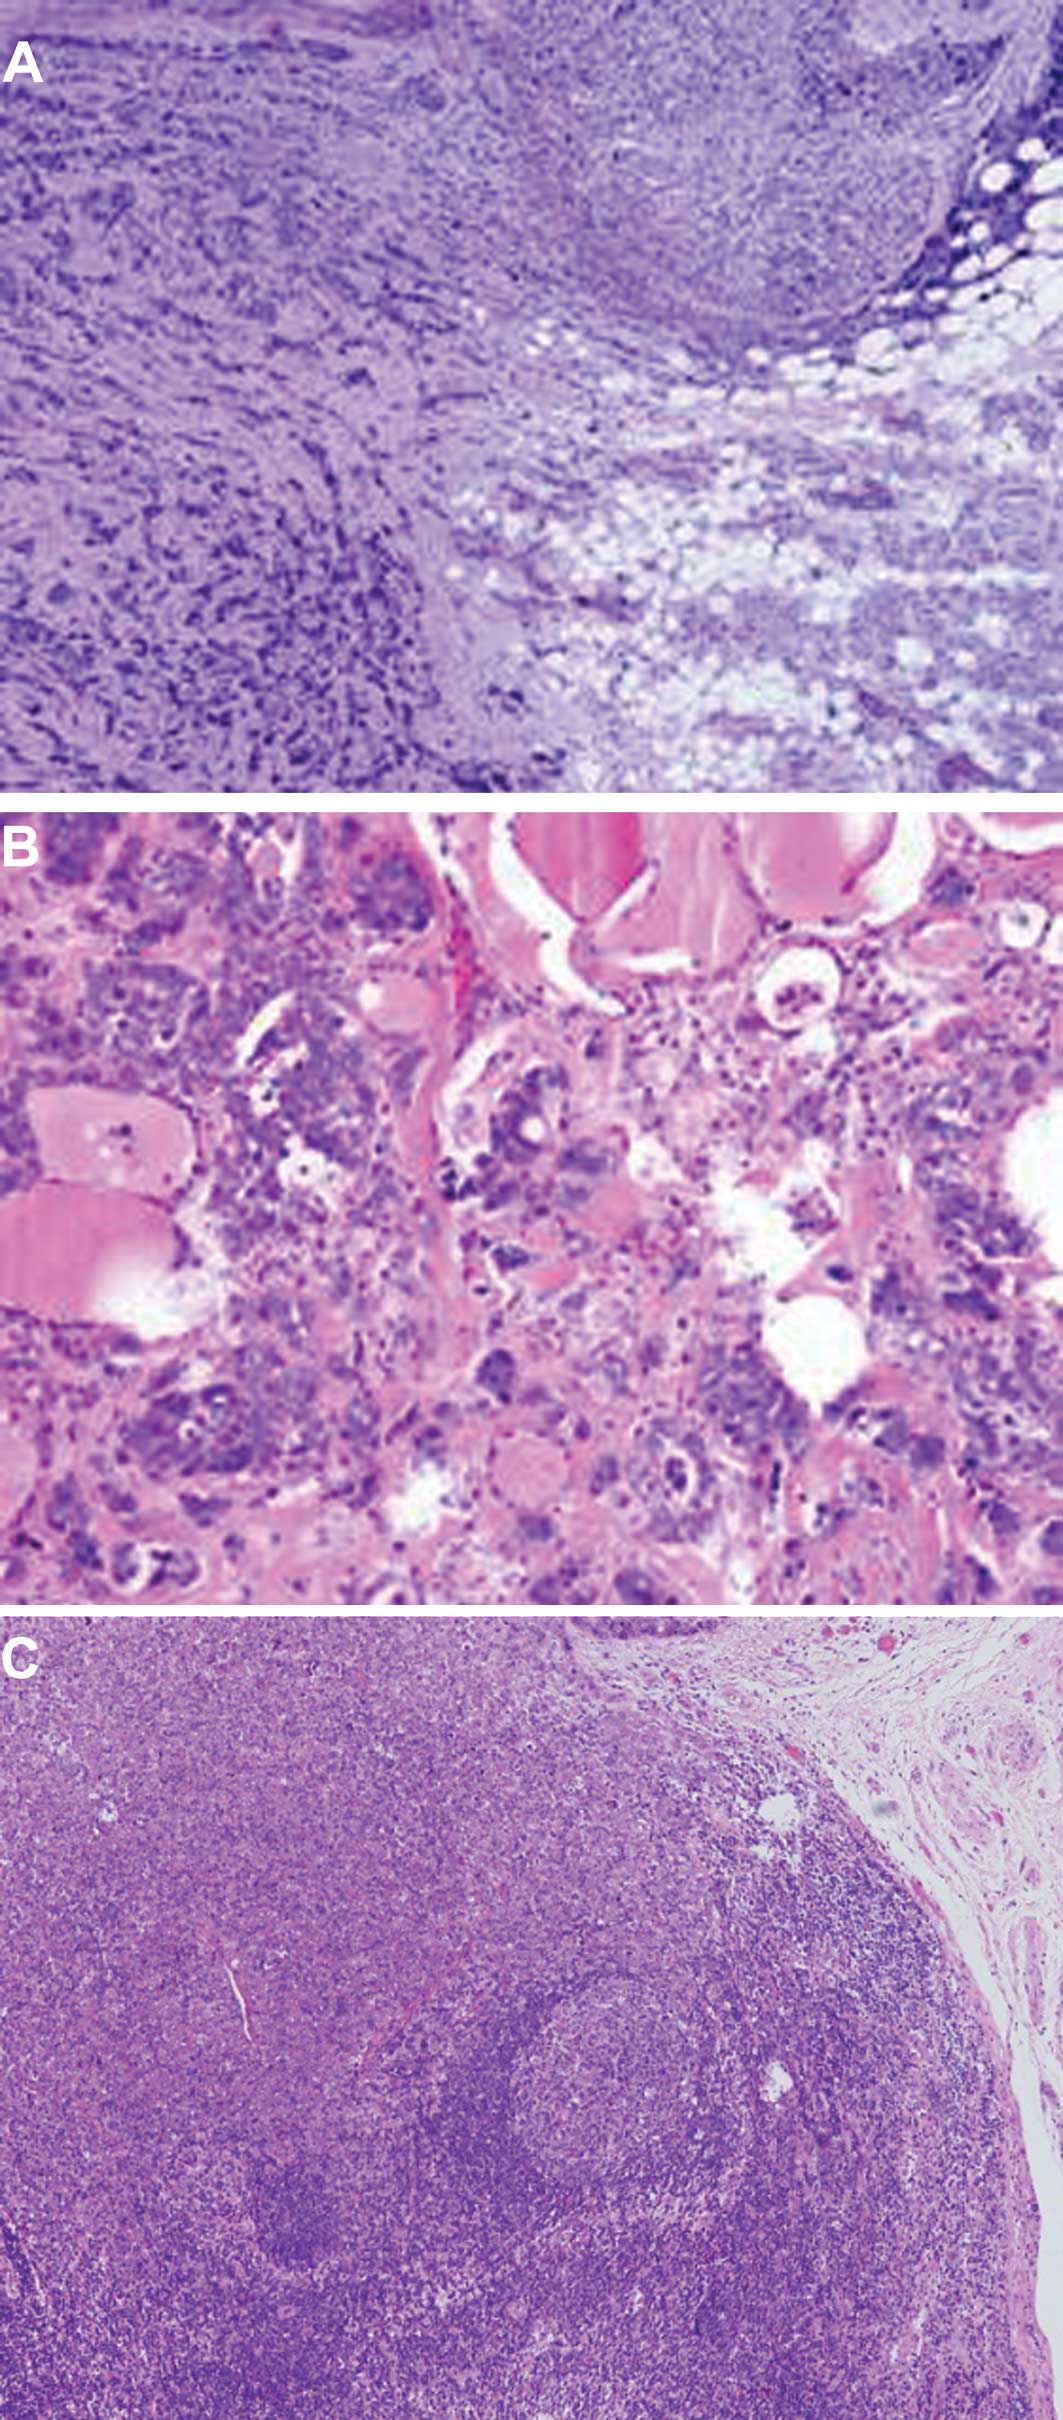

The parotid tumor showed nests or trabecular architecture divided by fibrous septa with no ductal or acinar differentiation (Fig. 2A). The neoplastic cells with a myxoid stroma, from the thyroid, exhibited mild cytological atypia and minimal cytoplasm without the ductal lumen structure (Fig. 2B). The neoplastic cells from the involved lymph nodes showed identical morphological features to the primary lesion in the parotid gland (Fig. 2C). The neoplastic cells showed positive immunoreaction for CK5, CK18, Calponin, S-100, Ki-67 and P63, respectively, in Fig. 3, with a strong to weak expression.

Figure 2

(A) The tumor showed nests or trabecular architecture divided by fibrous septa; H&E; magnification, × 100. (B) The tumor metastasized to the thyroid; H&E; magnification, × 200. (C) The tumor metastasized to the lymph nodes; H&E; magnification, × 40.

The cytomorphology and immunohistochemical findings were similar to those of the previously resected primary myoepithelial carcinoma (MCA) of the parotid gland. The original tumor exhibited an infiltrative multilobular growth pattern with increased mitotic activity (up to 8 mitoses per 10 high power fields) and proliferative rate (Ki-67 index of >75%).